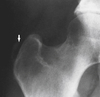

What is this? Possible tx?

Calcific tendinopathy of the supraspinatus tendon - pain during resorptive phase - pain in response to local chemical pathologic disorder or direct mechanical irritation - decreased ROM - Can dx with XR and US - tx with percutaneous needle lavage and steroid injection